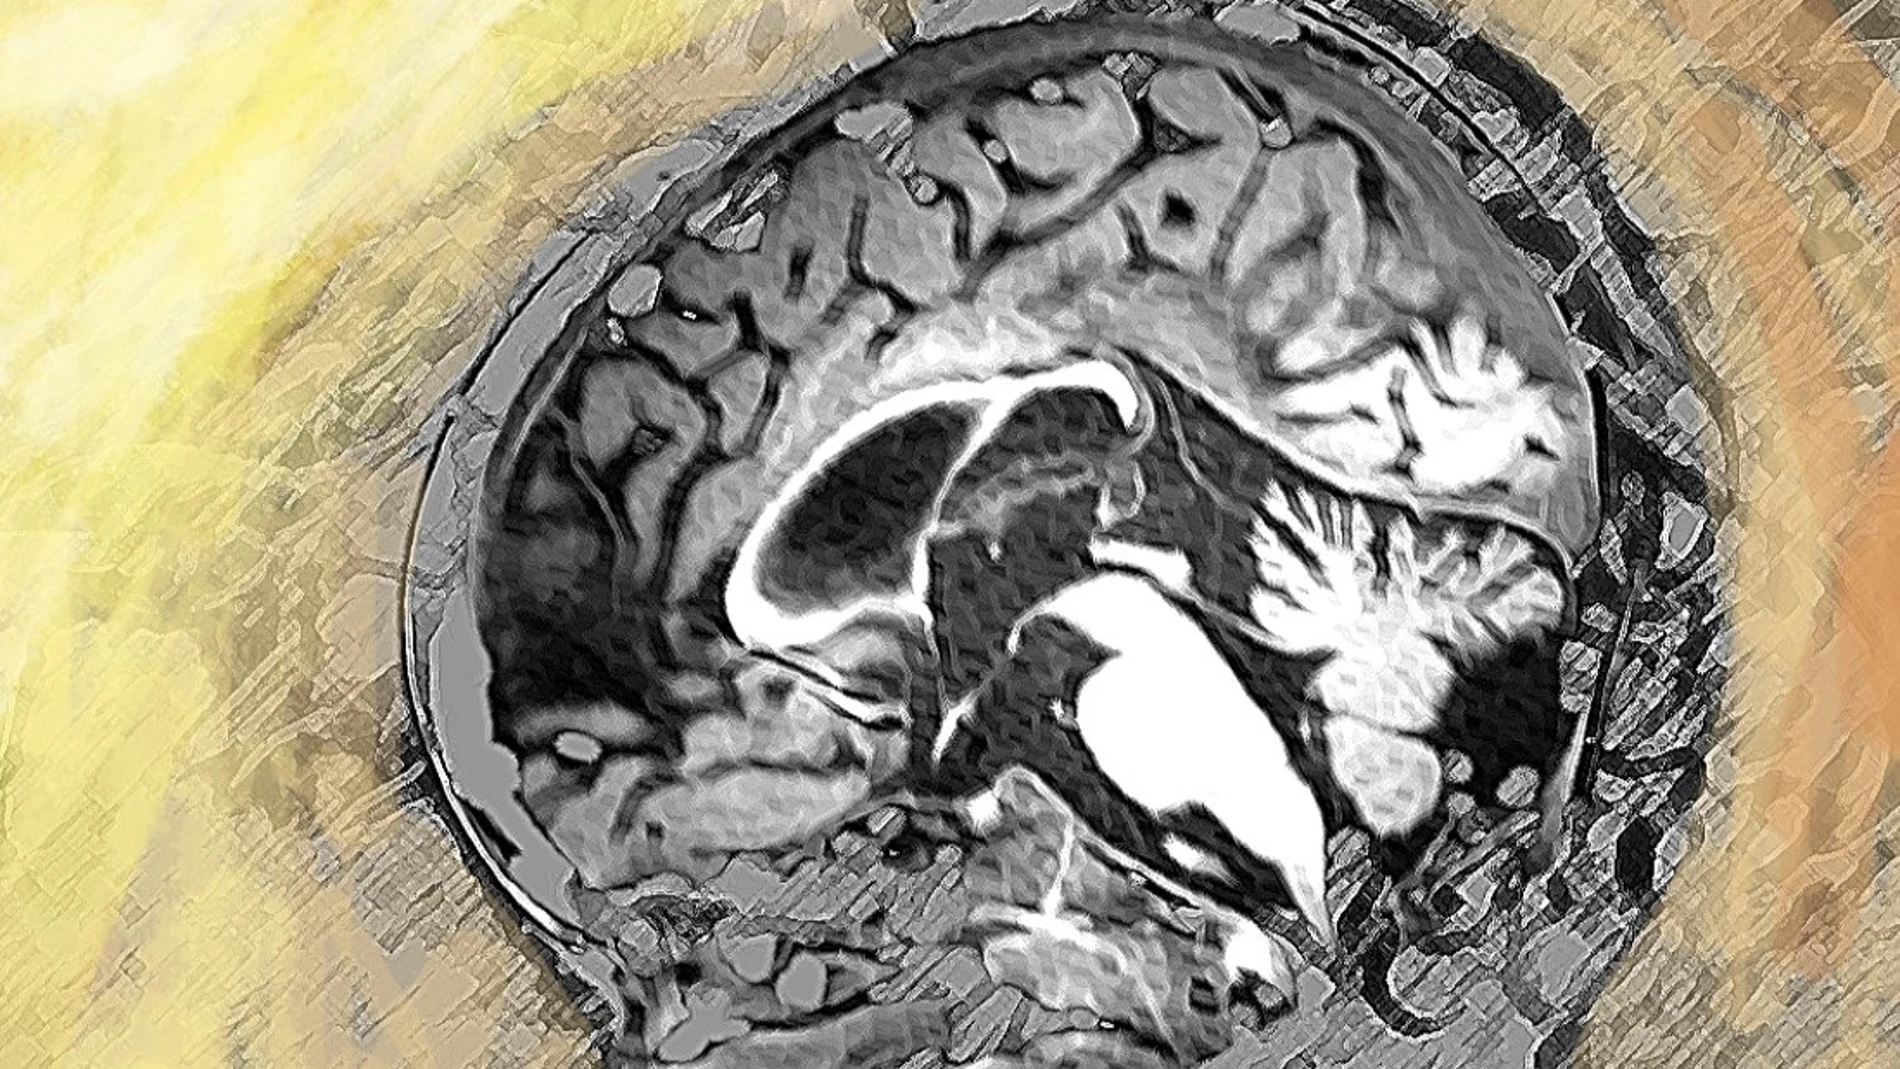

El gen implicado codifica una enzima que es una pieza clave en el metabolismo de los proteoglicanos, moléculas esenciales en el desarrollo del cerebro y la mielina, una sustancia vital que recubre las neuronas y permite la correcta conducción de los impulsos eléctricos entre ellas. Un mal funcionamiento de esta enzima provoca un tipo de leucodistrofia que incluye un grave defecto en la formación de la mielina y también del sistema esquelético.

Las leucodistrofias son enfermedades genéticas raras que afectan al sistema nervioso. Son muy severas y tienen mal pronóstico, con pocas opciones terapéuticas, aunque la terapia génica es prometedora en enfermedades como la adrenoleucodistrofia o la leucodistrofia metacromática. Hasta ahora se han identificado más de 150 genes causantes de leucodistrofias.